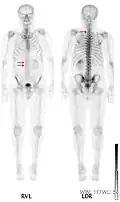

Knochenmetastasen

Knochenmetastasen unterschiedlicher Tumorerkrankungen können mit PET/CT sehr gut nachgewiesen werden. Das Verfahren ist sensitiver als die SPECT und erheblich sensitiver als die planare Skelettszintigrafie, jedoch auch aufwändiger und somit teurer. Je nach Tumorentität werden unterschiedliche Tracer verwendet, meist jedoch FDG und Natriumfluorid, beim Prostatakrebs auch 11C- oder 18F-Cholin. Metabolische Aktivität des Tumors ist mit Hilfe des Tracers FDG, die Reaktion des Knochens auf den Tumor mit der Natriumfluorid-PET/CT meist gut darstellbar (siehe Bildbeispiele).[33]

-

HDP-Skelettszintigramm eines Patienten mit Nierenkrebs: Die Knochenmetastasen im Halswirbelkörper 7 und in der Lendenwirbelsäule (LWK 1&2) sind aufgrund der geringen Auflösung der planaren Skelettszintigrafie nur zu erahnen. -

SPECT-Aufnahme des HDP Skelettszintigramms desselben Patienten; von den beiden Metastasen in der Lendenwirbelsäule ist nur eine einzige Läsion erkennbar; die Läsion in der Halswirbelsäule ist nicht dargestellt. -

FDG-PET desselben Patienten: Die osteolytische Knochenmetastase im Halswirbelkörper reichert FDG nicht an und ist nur im CT erkennbar. Die beiden weiteren Knochenmetastasen in der Lendenwirbelsäule werden dagegen auch in der FDG-PET/CT dargestellt. -

Natriumfluorid-PET/CT desselben Patienten: Die osteolytische Knochenmetastase in der Halswirbelsäule zeigt einen extremen Uptake und ist klar erkennbar. Die beiden weiteren Knochenmetastasen in der Lendenwirbelsäule stellen sich in der PET/CT-Aufnahme ebenfalls sehr gut dar. -